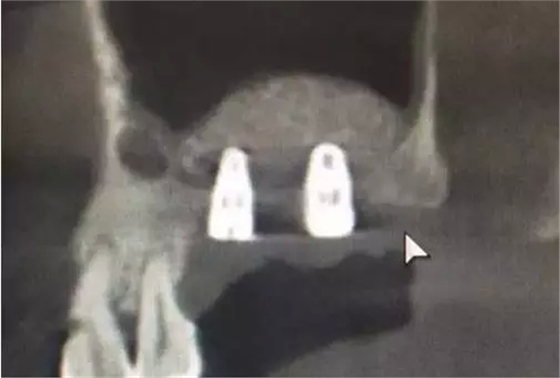

植入兩顆植體。

術(shù)后6,7牙位CT片,顯示充足的植骨量。

整個(gè)手術(shù)時(shí)間僅20分鐘,充分體現(xiàn)了:安全、方便、快捷的原則。